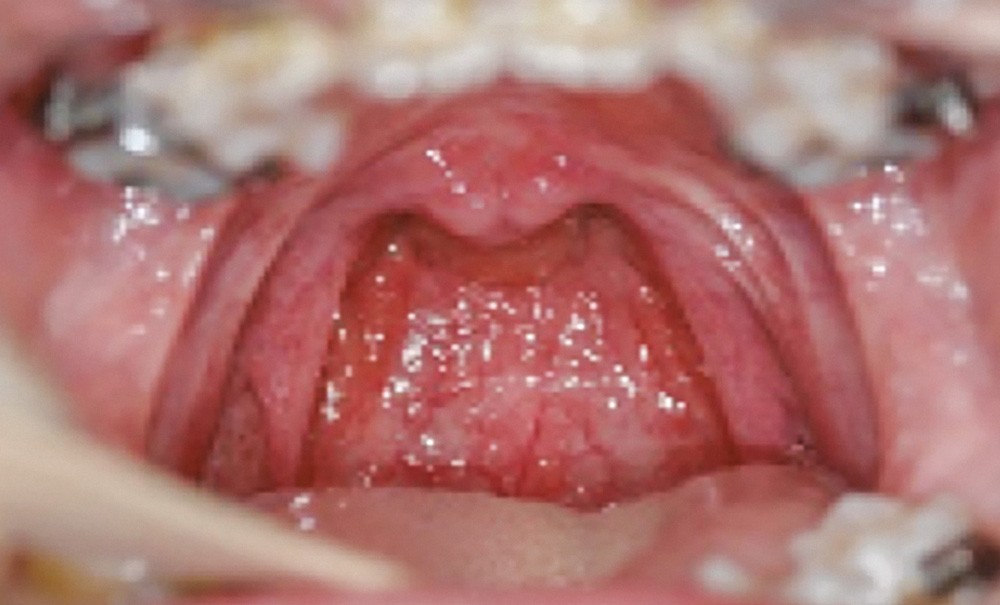

La phonation est un élément capital dans les échanges inter-individus. Les troubles de l’articulation des sons de la parole et du langage que peuvent présenter les enfants en cas d’incompétence vélo-pharyngée demeurent la séquelle la plus préjudiciable dans leur vie au quotidien.

Aussi, dans le cadre du traitement des fentes labio-palatines (FLP), la participation et l’implication d’orthophonistes spécialisés au sein de l’équipe pluridisciplinaire est précoce et régulière. Cette présence systématique favorise l’évolution de la prise en soin globale des enfants.

Nos connaissances des troubles liés à l’incompétence vélo-pharyngée [2, 3, 4, 5] s’étant enrichies, le suivi orthophonique précoce a pour objectif de favoriser la mobilité du voile…